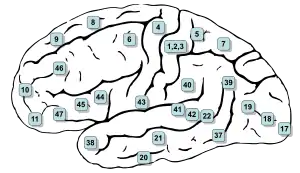

Image of brain with Brodmann areas numbered | |

Brodmann area 12 is a subdivision of the cerebral cortex of the guenon defined on the basis of cytoarchitecture.[1][2] It occupies the most rostral portion of the frontal lobe. Brodmann-1909 did not regard it as homologous, either topographically or cytoarchitecturally, to rostral area 12 of the human. Distinctive features (Brodmann-1905): a quite distinct internal granular layer (IV) separates slender pyramidal cells of the external pyramidal layer (III) and the internal pyramidal layer (V); the multiform layer (VI) is expanded, contains widely dispersed spindle cells and merges gradually with the underlying cortical white matter; all cells, including the pyramidal cells of the external and internal pyramidal layers are inordinately small; the internal pyramidal layer (V) also contains spindle cells in groups of two to five located close to its border with the internal granular layer (IV).